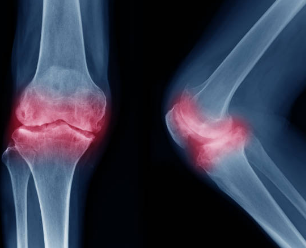

์ด์ ํจ๊ป X-ray ์ดฌ์์ ํดํ์ฑ ๊ด์ ์ผ ์ง๋จ์ ์์ด ๊ฐ์ฅ ํต์ฌ์ ์ธ ๋๊ตฌ ์ค ํ๋์ ๋๋ค. X-ray๋ ๋ผ์ ์ํ๋ฅผ ๋ช ํํ๊ฒ ๋ณด์ฌ์ฃผ๊ธฐ ๋๋ฌธ์, ์ฐ๊ณจ์ด ์ผ๋ง๋ ๋ณ์ ๊ด์ ๊ฐ๊ฒฉ์ด ์ข์์ก๋์ง, ํน์ ๋ผ ๋์ ๊ณจ๊ทน(๋ผ๊ฐ ์๋ผ๋ ๊ฒ)์ด ํ์ฑ๋์๋์ง ๋ฑ์ ์ก์์ผ๋ก ํ์ธํ ์ ์๊ฒ ํด ์ค๋๋ค. ์ด๋ ํดํ์ฑ ๋ณํ์ ์ ๋๋ฅผ ๊ฐ๊ด์ ์ผ๋ก ํ์ ํ๋ ๋ฐ ํฐ ๋์์ ์ค๋๋ค.

๋ง์ฝ X-ray๋ง์ผ๋ก๋ ์ ํํ ์ง๋จ์ด ์ด๋ ต๊ฑฐ๋, ์ฐ๊ณจ ์์ ์ ๋, ์ฃผ๋ณ ์ธ๋๋ ํ์ค์ ์ํ ๋ฑ ๋์ฑ ์์ธํ ์ ๋ณด๊ฐ ํ์ํ ๊ฒฝ์ฐ์๋ MRI(์๊ธฐ ๊ณต๋ช ์์) ๊ฒ์ฌ๋ฅผ ์ถ๊ฐ๋ก ์ํํ๊ธฐ๋ ํฉ๋๋ค. MRI๋ ์ฐ๊ณจ, ์ธ๋, ๊ทผ์ก ๋ฑ ์ฐ๋ถ ์กฐ์ง์ ์ ๋ฐํ๊ฒ ๋ณด์ฌ์ฃผ๊ธฐ ๋๋ฌธ์, X-ray๋ก๋ ๋ณผ ์ ์๋ ๋ฏธ์ธํ ์์์ด๋ ์ผ์ฆ๊น์ง ํ์ ํ์ฌ ์ง๋จ์ ์ ํ์ฑ์ ๋์ฌ์ค๋๋ค.